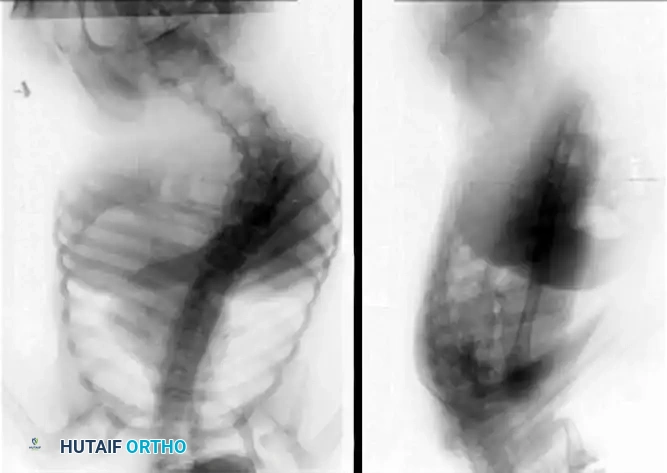

Fig. 30-43 A, Posteroanterior view of spine of patient with spastic quadriplegic cerebral palsy with 73-degree thoracolumbar scoliosis and pelvic obliquity. B, Lateral view of spine of same patient shows progressive lumbar lordosis. This deformity was believed to contribute to increased skin pressures and seating diffi culties. (From McCarthy JJ, D’Andrea LP, Betz RR, et al: Scoliosis in the child with cerebral palsy, J Am Acad Orthop Surg 14:367, 2006.)

As demonstrated in the imaging above, severe thoracolumbar curves in spastic quadriplegia rapidly progress to structural pelvic obliquity, leading to asymmetric ischial seating pressures and a high risk of decubitus ulceration.